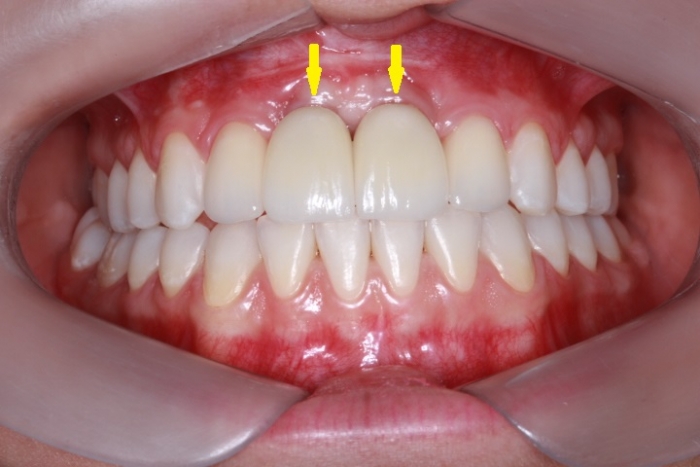

Próteses Definitivas em Porcelana

Sorriso Final, em 2016